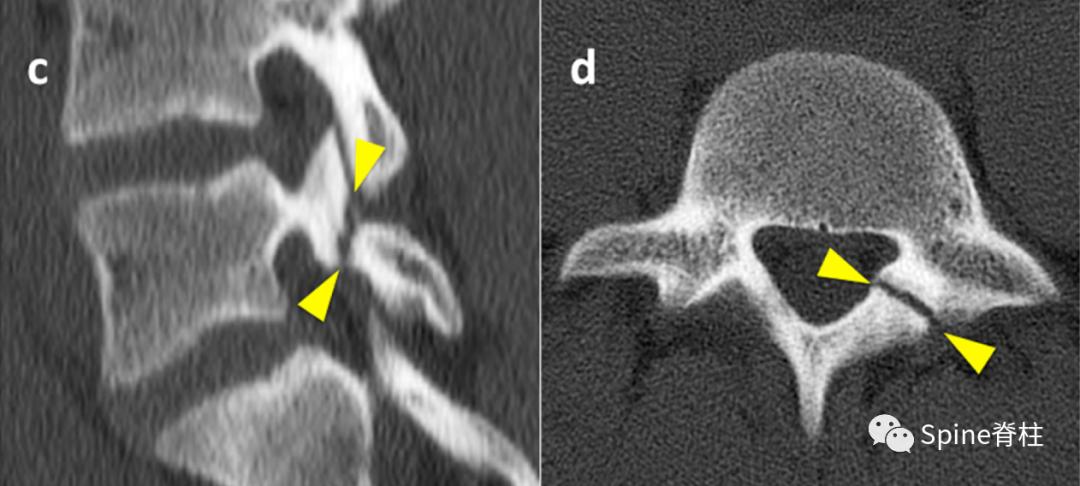

2. 腰椎峡部和峡部裂在CT片上的表现

PMID: 30396669

峡部裂的CT分型 :A=早期(线性骨折),B=进展期(明显的骨间隙),C=终末期(假关节形成)

右侧为进展期峡部裂,左侧为早期峡部裂,右侧图片是支具固定7个月后愈合